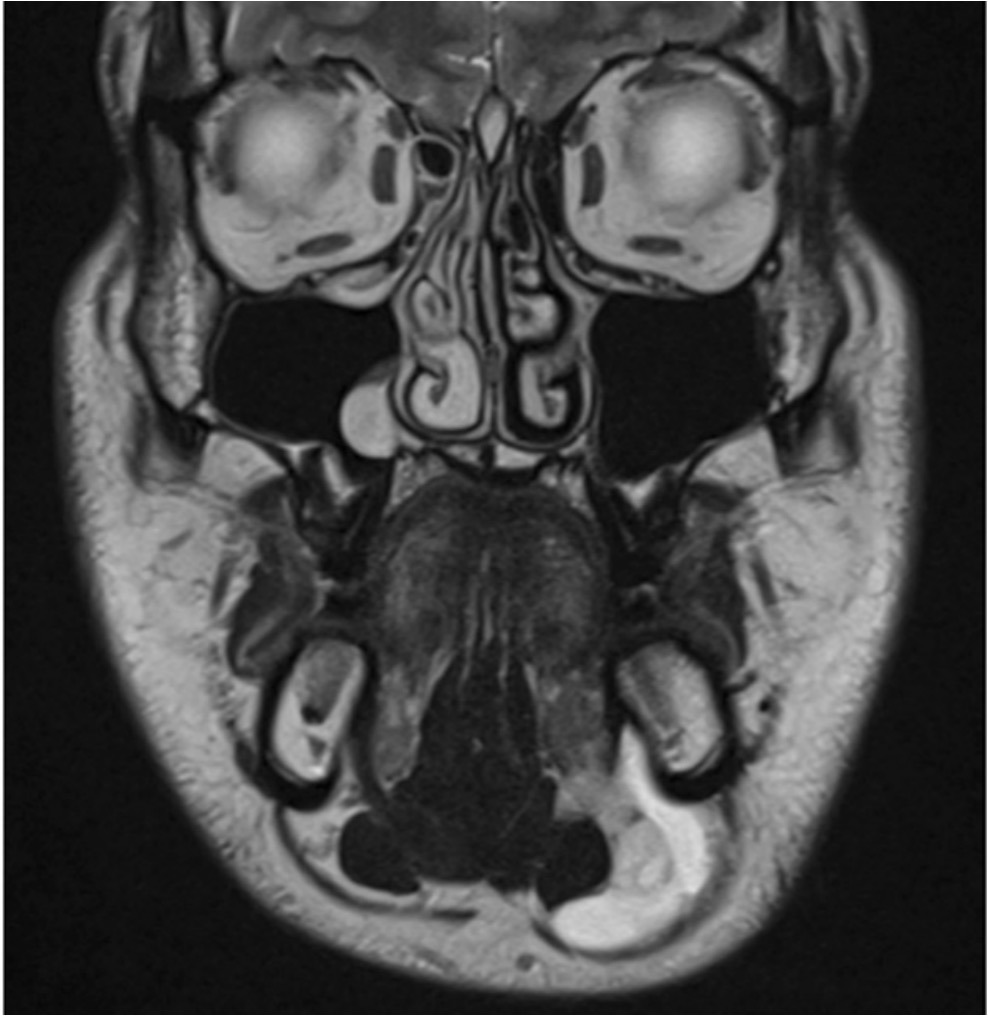

- Imaging

- Magnetic Resonance Imaging

- The presence of a ‘‘tail sign’’ (indicating communication between the collapsed sublingual and submandibular space over the posterior edge of the mylohyoid muscle) supports the diagnosis of a plunging ranula. Will be seen on all imaging modalities.